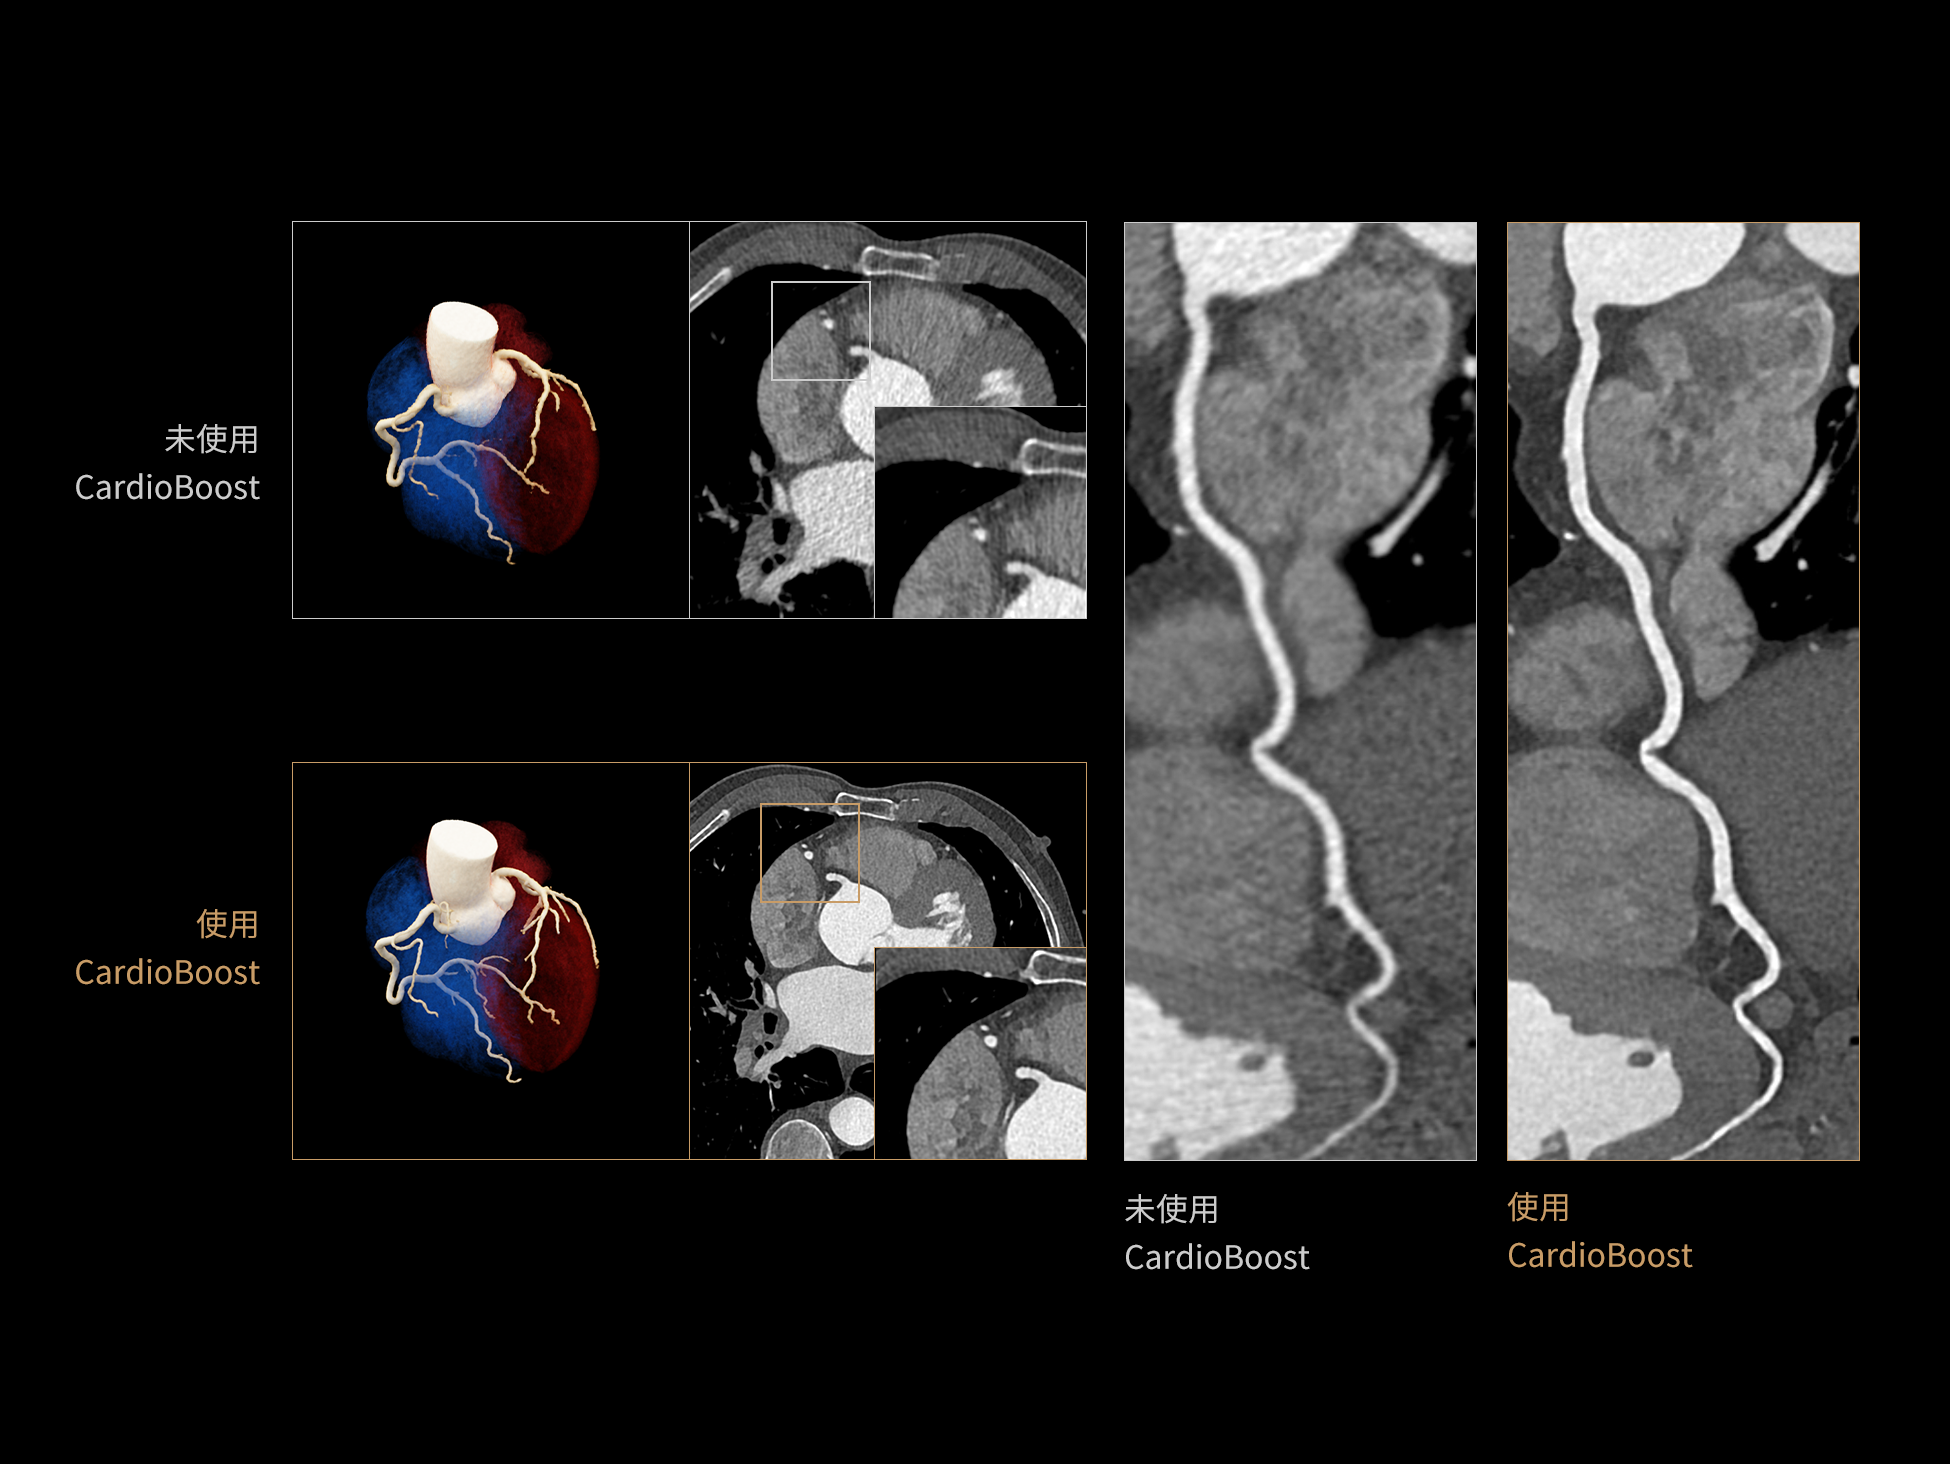

CardioBoost:专属网络设计,重塑心脏影像表现

目前心脏的 CT 检查还存在辐射剂量偏高、空间分辨率不足、 致密钙化伪影影响冠脉狭窄程度评估等方面的限 制[1][2]。CardioBoost 技术专为心脏 CT 高清成像而开发,通过 3D 神经网络的深度学习技术,利用先进的注意力机制在识别关键成像特征方面的出色表现,能够精确地聚焦于斑块、支架以及微小血管等关键细节,清晰展示这些结构与冠脉血管的边界,从而显著提高诊断的准确性,并提升医生的诊断信心。创新的 CardioBoost 心脏图像重建算法,不仅实现了图像清晰度的提升和伪影的去除,更能在减少辐射剂量的同时,保证心脏图像的高质量和图像纹理的自然。

采用 3D 神经网络的空间结构优势与精细的组织分类能力,CardioBoost 技术优化了组织对比,高清展示血管斑块,使斑块与血管边缘的轮廓清晰可辨,提升斑块诊断与评估的精确性。

借助 3D 神经网络设计、空间注意力机制聚焦与特征强化作用,CardioBoost技术提升图像的空间分辨率,实现冠脉支架的高清成像,对支架形态与管腔通畅度的评估更精准。

CardioBoost 整合先进的 3D 神经网络和空间注意力机制,大幅增强数据处理的速度与精确度。该技术能有效抑制由致密钙化引起的晕状伪影,清晰展现钙化斑块的原始结构和大小,对冠脉狭窄的评估更加精确可靠。

对比度强化模块

分辨率强化模块

伪影抑制模块